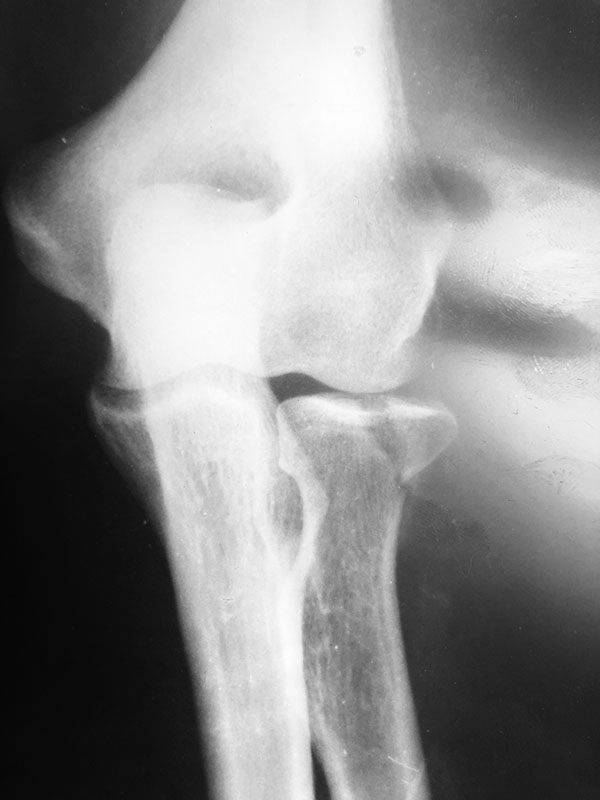

Здравствуйте. Мужчина 50 лет. Травма 25 августа 2018 года. Рентген был

расценён как ушиб(снимки прилагаются). В дальнейшем пациента беспокоила

боль, ограничение подвижности. Из поля зрения медицины выпал. При

повторном обращении 9 октября выполнен повторный снимок- зам.

консолидирующийся перелом головки луча. Подскажите пожалуйста с тактикой

лечения.

P.S.:Собственно у пациента про- супинационные движения в полном объёме

за исключением дефицита супинации в 10^ и сгибательная контрактура

локтевого сустава около 15^. Все это время сустав без фиксации.